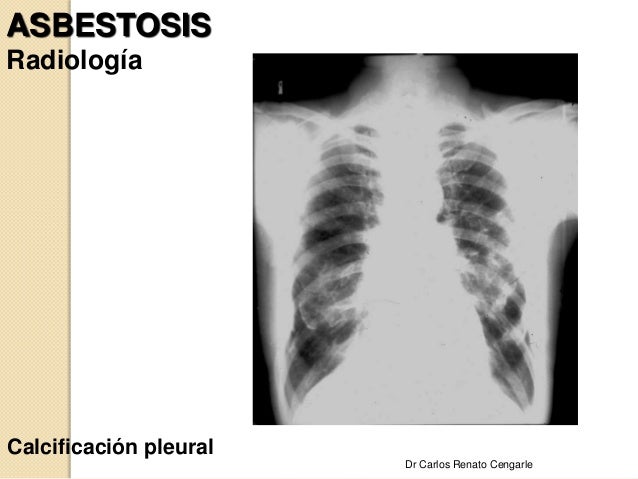

National claims center file your mesothelioma claim today. Find asbestosis treatment. Browse & discover useful results! Asbestosis treatment asbestos network. Healthpixie has been visited by 10k+ users in the past month. Asbestosis in lungs symptoms, causes & treatment options. Treatment options. Asbestosis is an irreversible condition. With the exception of lung transplantation, all asbestosis treatment options are palliative, meaning they address the symptoms of asbestosis to improve the patient’s quality of life. Because the condition gets worse over time, patients require increased treatment as they age. Asbestosis treatment & management medscape reference. Free case evaluation experienced mesothelioma asbestos death attorneys. Mesothelioma death diagnosed with mesothelioma?. Listed with the bbb a+ rating. Asbestosis treatment conditions & treatments ucsf. Asbestosis treatment. The first step of asbestosis treatment is to end all contact with asbestos, although most people have been exposed in the past and often are retired altogether by the time they develop symptoms of the disease. Smoking multiplies the risk of lung cancer in asbestos and therefore must be stopped if still ongoing. Asbestosis can be difficult to diagnose because its signs and symptoms are similar to those of many other types of respiratory diseases. A variety of diagnostic tests might be needed to help pinpoint the diagnosis. Imaging tests. Chest xray. Advanced asbestosis appears as excessive whiteness in your lung tissue.